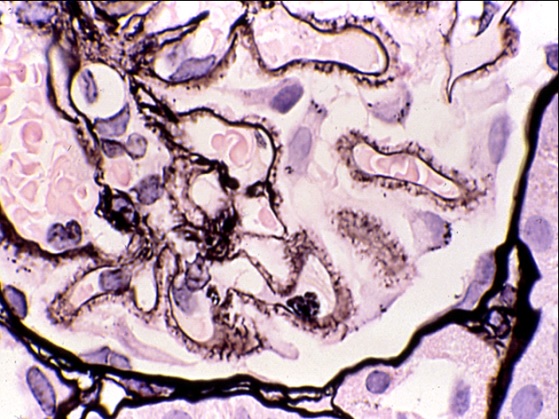

肾活检病理由于疾病具有独特的发病机制和特点,对病理技术要求很高,常规的HE染色需要薄切片,还要结合多种特殊染色(图1)、免疫荧光/组化(图2)及透射电镜检查(图3),才能进行正确诊断,为患者的治疗和预后判断提供依据。

图1,膜性肾病,PASM染色。